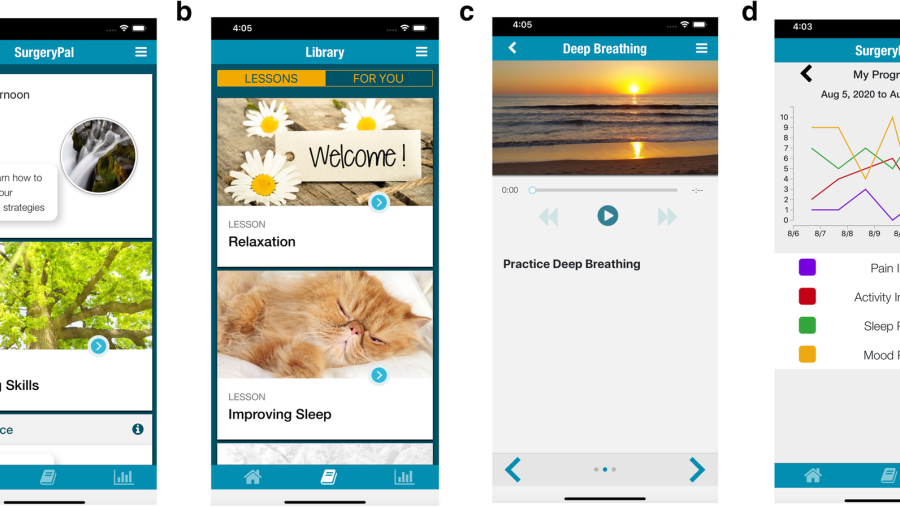

Image

Finding the Best Treatment for Individual Patients